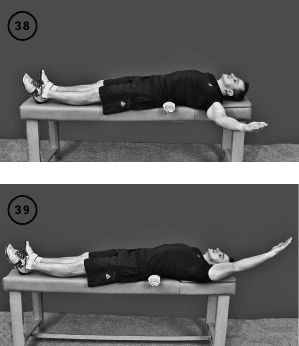

Упражнение «Полет – плечо назад»

Исходное положение – прежнее. Левое плечо свободно свисает с кушетки. Фаза изометрического напряжения: поднимаете левое плечо назад до горизонтального уровня или чуть выше – на сколько позволяет объем движения в плечевом суставе. Удерживаете эту позицию изометрического напряжения в течение 20–30 секунд.

Фаза растяжения: расслабляете руку, и она свободно свисает вниз, растягивая своим весом мышцы плечевого сустава. Повторить 1–3 раза, выполнить упражнение для правого плеча (ил. 38–40).